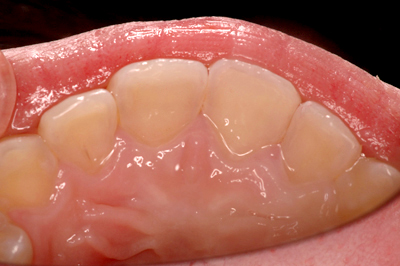

矯正治療例

施術前

施術中

施術後